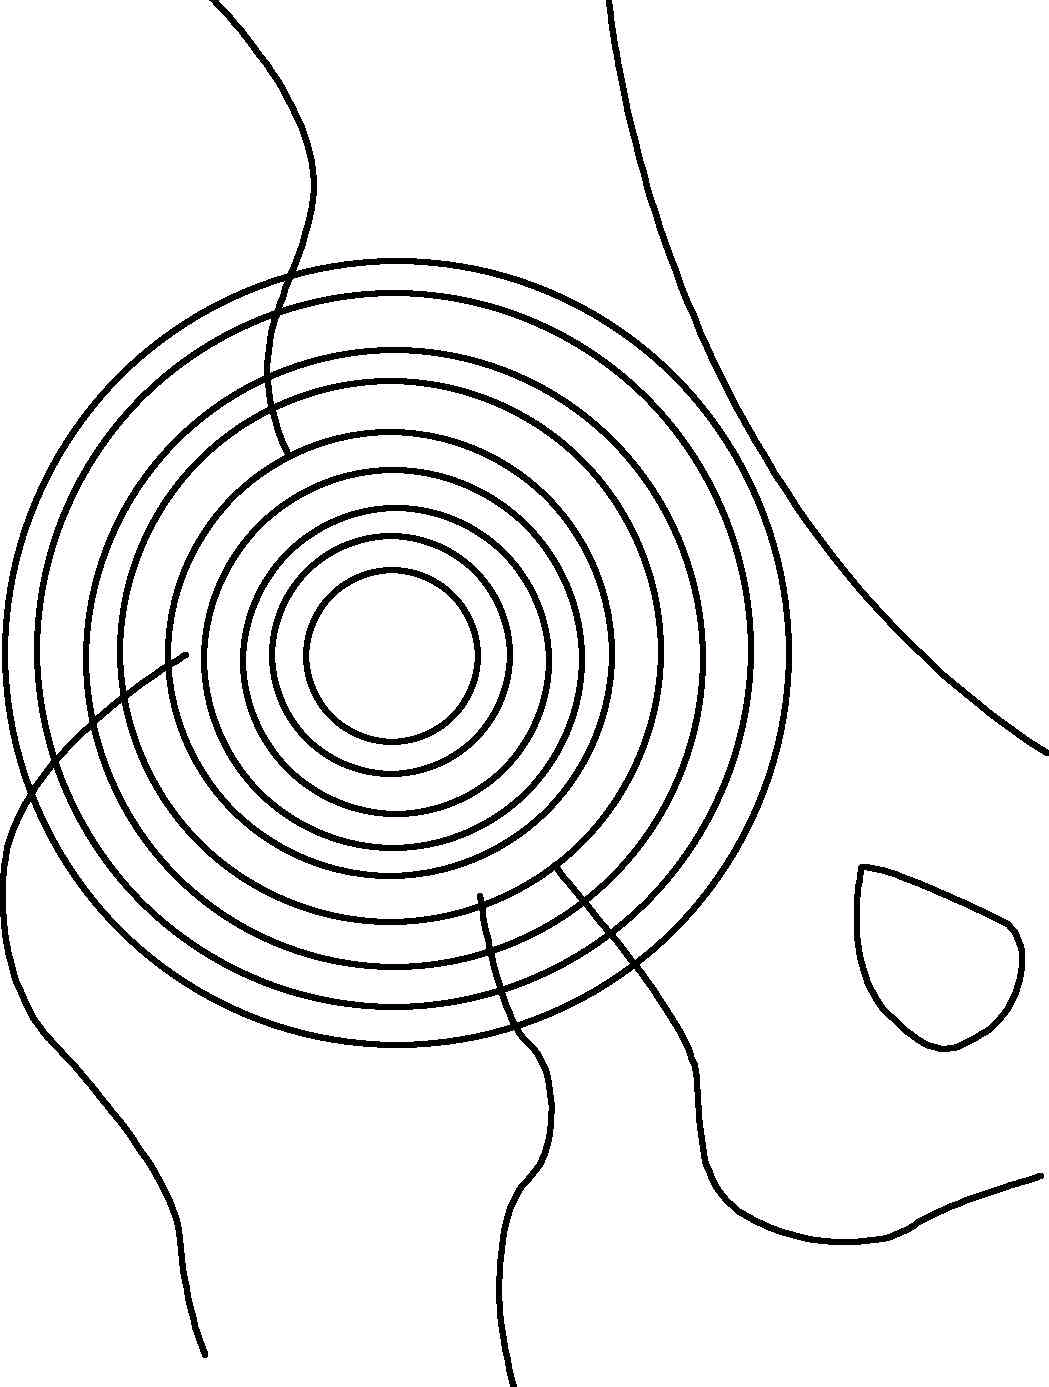

股骨头中心;Mose同心圆法确定股骨头中心点

大多数学者采用Mose同心圆法确定股骨头中心点。